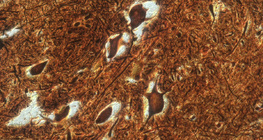

200х увеличение

100х увеличение

50х увеличение

300х увеличение

400х увеличение

600х увеличение

160х увеличение

1000х увеличение